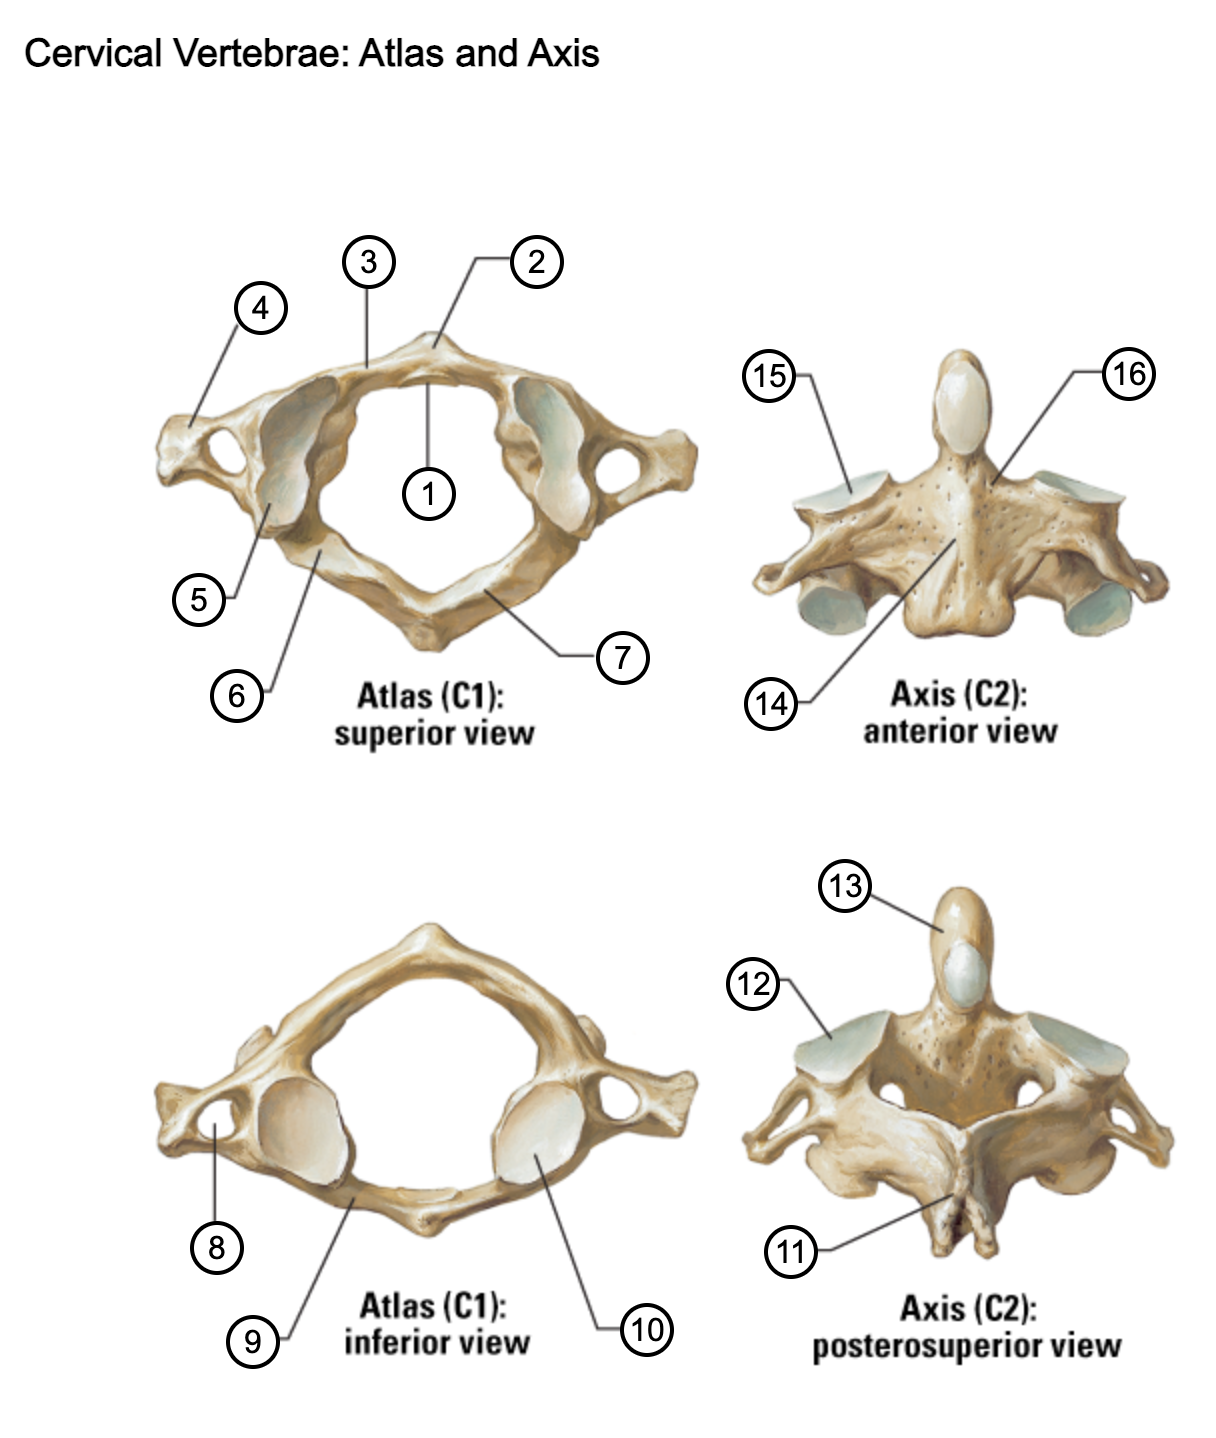

1

facet for dens

2

anterior tubercle

3

anterior arch

4

transverse process

5

superior articular surface of atlas

6

groove for vertebral artery

7

posterior arch

8

transverse foramen

9

anterior arch

10

inferior articular surface of atlas

11

spinous process

12

superior articular facet

13

dens of axis

14

body of axis

15

superior articular facet for atlas

16

pedicle of vertebral arch